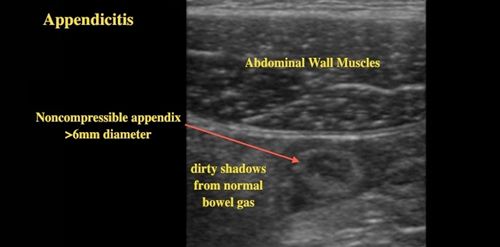

Siêu

âm rất chính xác (specific) trong việc xác định bạn không bị sưng ruột

dư, nếu siêu âm cho thấy rõ cái ruột dư của bạn hoàn toàn bình thường,

chả sưng to tí nào cả, ta có thể chắc ăn là bạn không bị sưng ruột dư.

Nhưng độ nhạy (sensitivity) của nó chỉ khoảng 86%, tức nó không khám phá

được 14% các trường hợp thực sự sưng ruột dư.